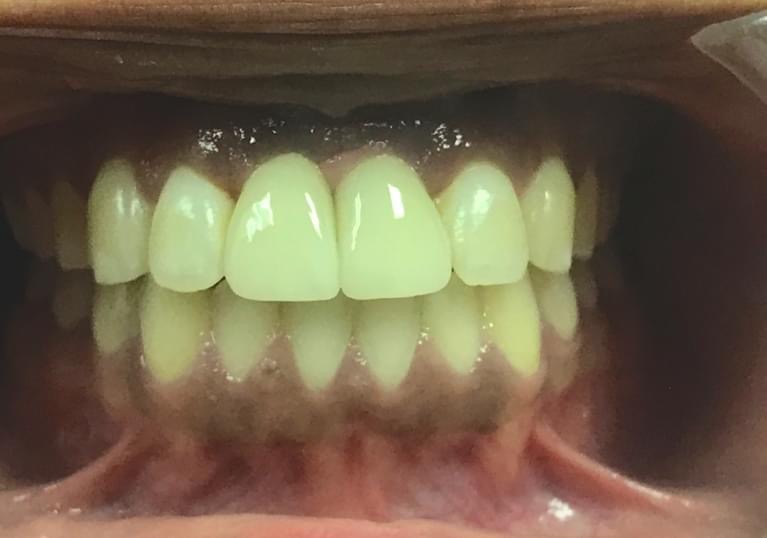

Single Implant Replacing two missing front teeth:

Single Implants replacing two Front teeth